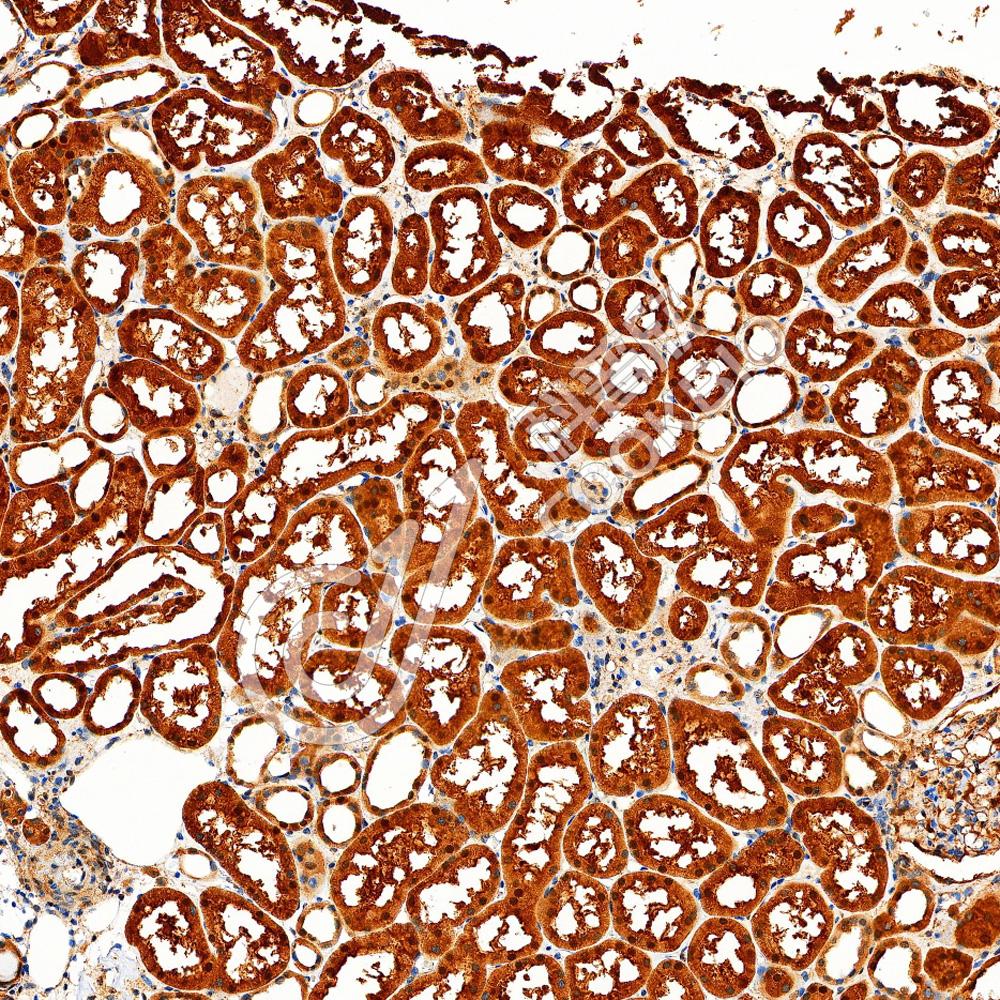

IHC检测Myeloperoxidase蛋白(货号 K2360048).

样品: 人扁桃体, 4%多聚甲醛 (货号KSG1101) 固定12-24小时.

抗原修复: 柠檬酸抗原修复液(干粉, pH 6.0) (KSG1201), 高压锅均匀喷气计时2分钟.

—抗: 1: 1000稀释, 4℃ 孵育过夜.

二抗: S-vision免疫组化多聚二抗(山羊抗小鼠), 即用型(货号KB3903), 室温孵育20分钟.